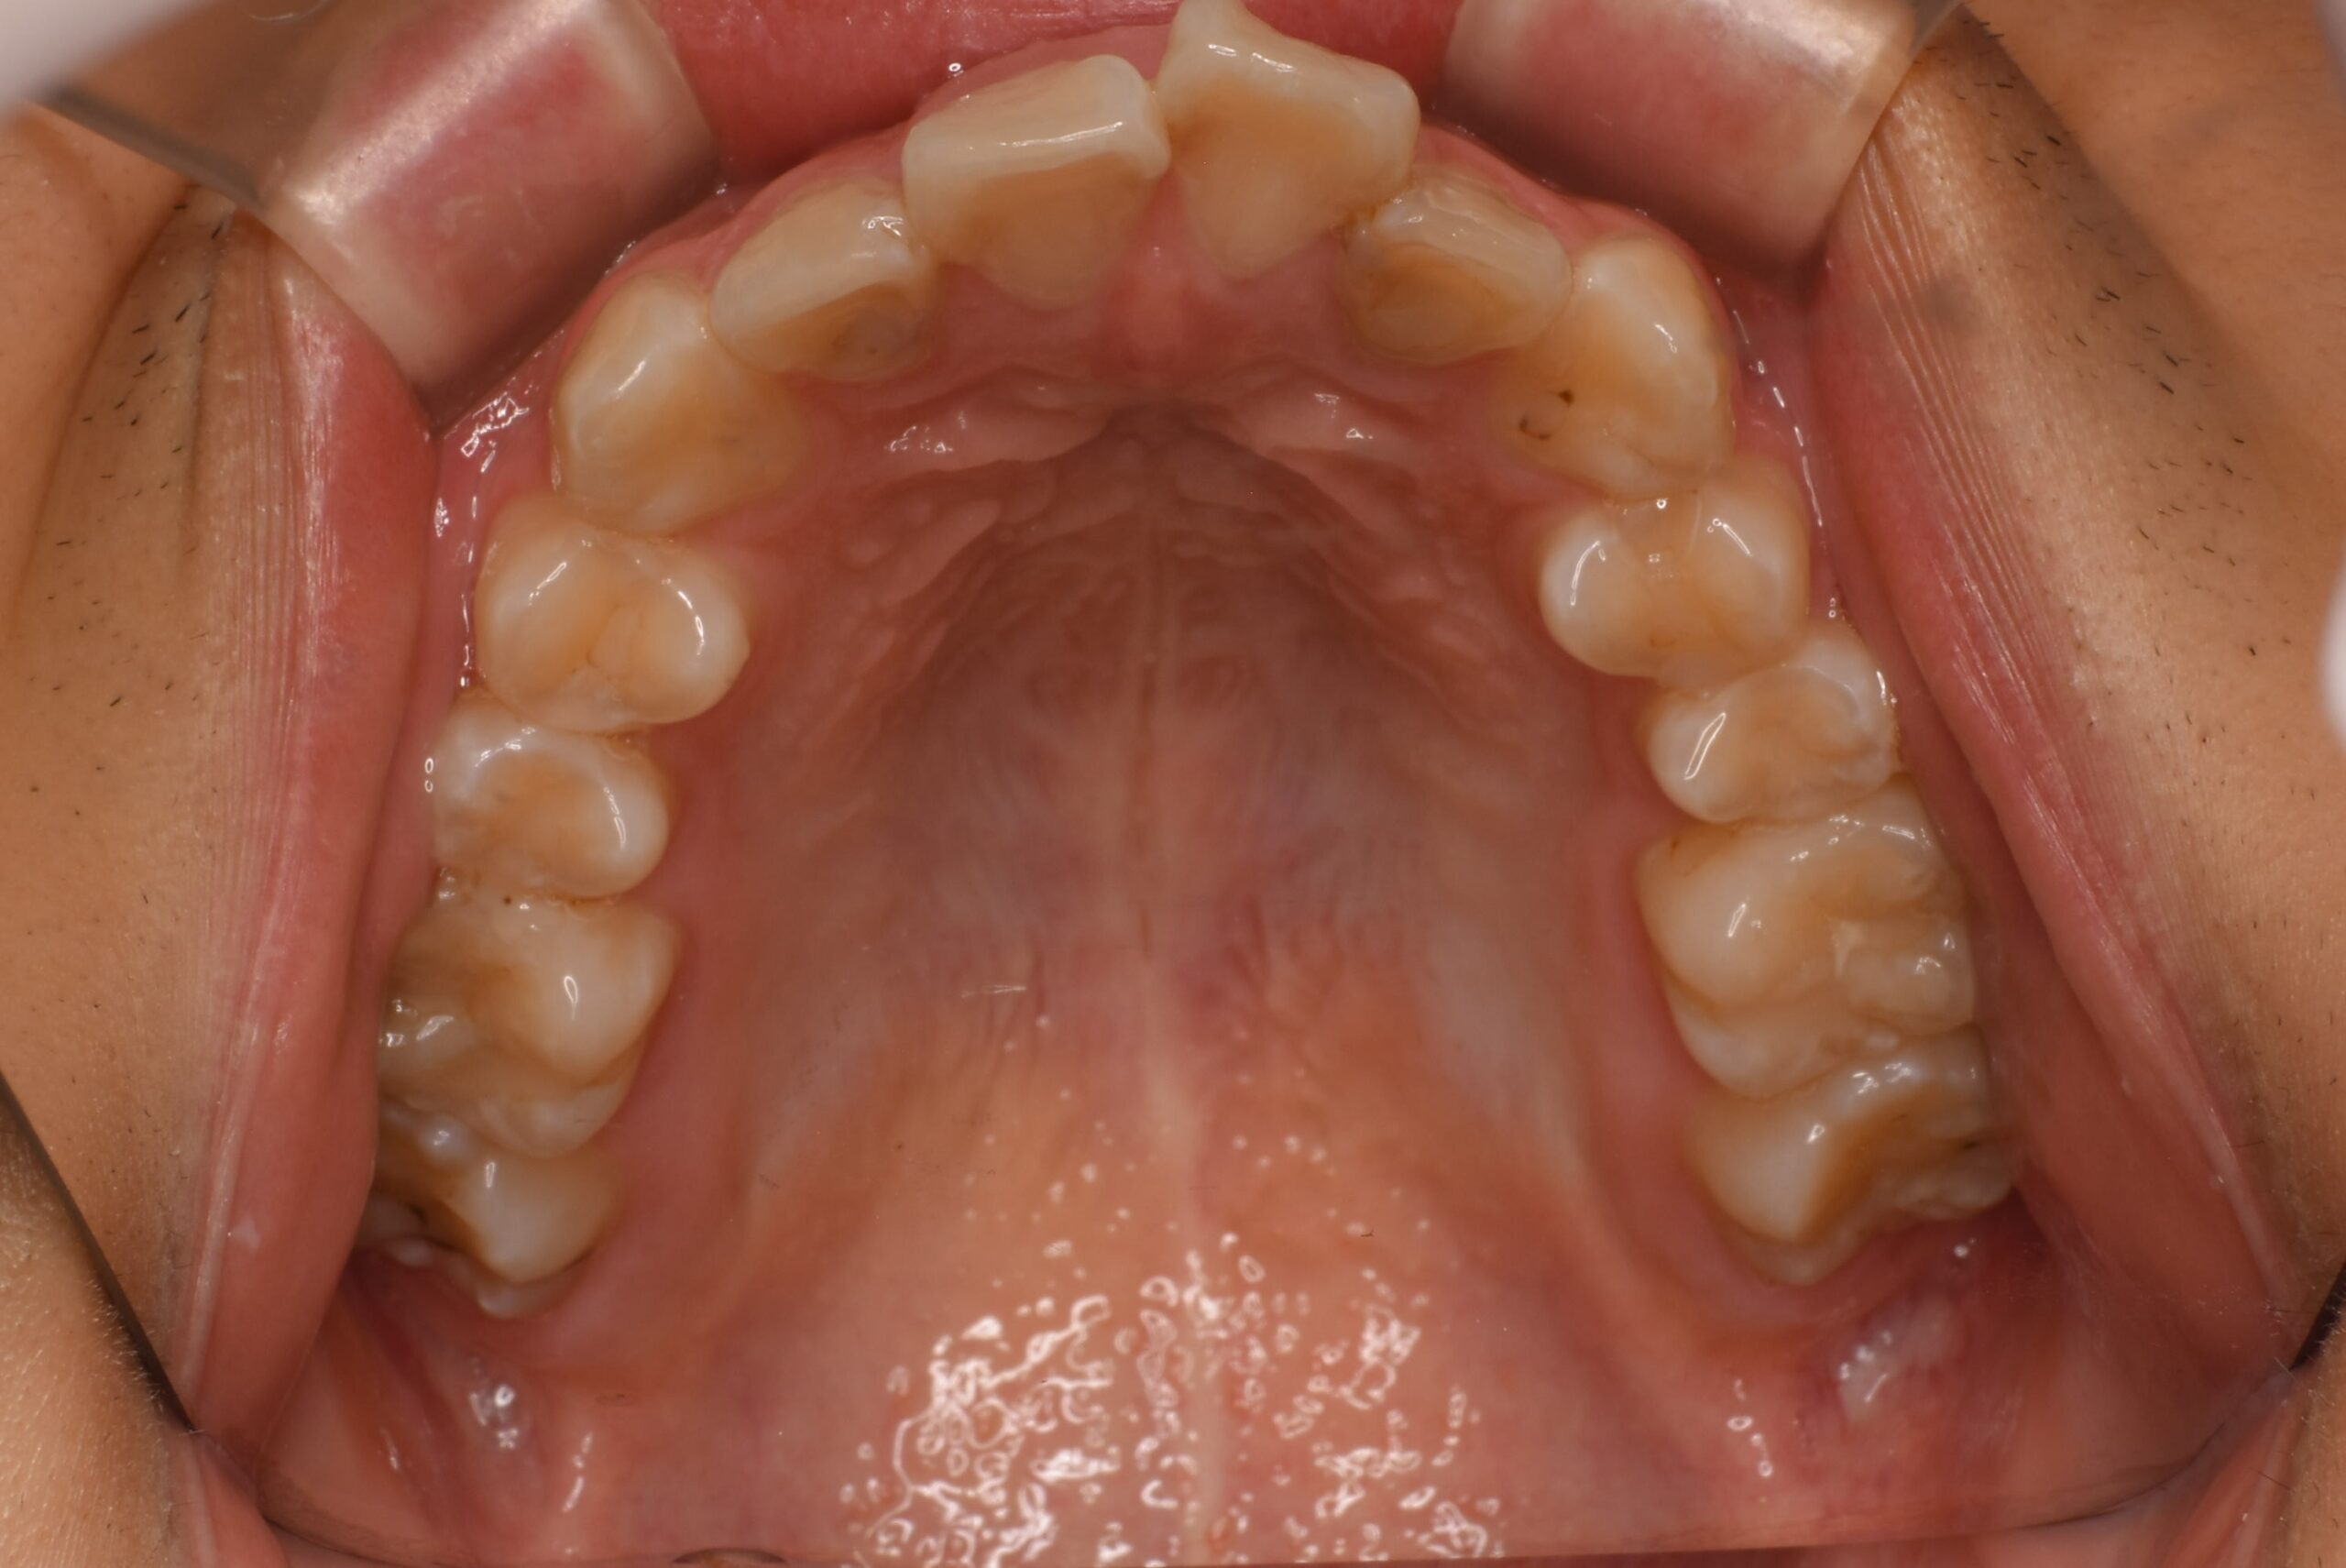

治療前_上顎咬合面

| 治療内容 | 患者様は、上の前歯の突出や不揃いな歯並びに加え、咬みにくさや歯のサイズ感にも悩まれており、目立たない方法での矯正治療をご希望され来院された。 診査の結果、前歯部の叢生と上顎前突を認めたが、骨格的には非抜歯での矯正が適応可能と判断した。永久歯列期でのインビザラインによる非抜歯矯正を計画した。 治療は、マウスピース型矯正装置「インビザライン」を使用した。歯の移動スペースを確保するため、必要最小限の歯間削合(歯と歯の間をわずかに削る処置)を行い、歯列全体を整えながら、前歯の位置・傾斜を調整した。 また、診査時に歯の表面に脱灰(初期の虫歯)を認めたため、セルフケア指導などの予防処置も並行して実施。歯列の改善とともに、口腔内の健康維持にも配慮した治療を行った。 |